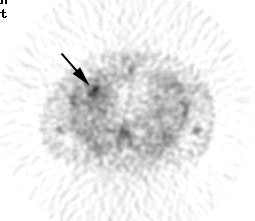

False positive Neotect exam: CT scan demonstrated an irregular nodule within the right middle lobe. Transaxial Neotect image demonstrated abnormal tracer accumulation in the lesion. The lesion was surgically resected and found to be related to fibrosis and chronic inflammation. Although very sensitive, the Neotect exam does suffer from a lower specificity and the potential for false positive exams. Case courtesy Dr. Jamie Montilla. |